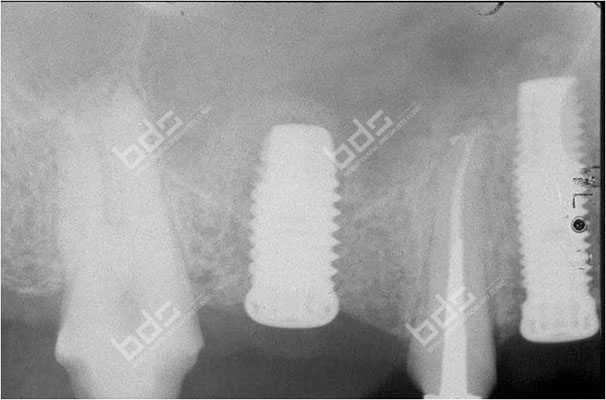

Dental Implants

Dental implants is a highly predictable procedure for the replacement of missing teeth, restoring in a very effective way both function and aesthetics. Dentures ,when loose, can cause severe personal and social handicaps that can be overcome by using implant supported fixed restorations. Implants can also serve to replace one or several teeth and save healthy adjacent teeth from being used as support for fixed bridges. The procedure can be very simple or more complex depending on the severity of the case. Implants used nowadays are mostly made of medical grade titanium. They are placed in the jaw and connected to abutments to serve as support for crowns or bridges.

Implant supported crowns are so natural looking ! Cad Cam technologies and innovative restorative materials give to the crown a perfect esthetic result. You will forget that you ever lost a tooth. your confidence is regained and your self image is completely restored. you do not need to hide your smile anymore nor feel embarrassed because of ill-fitting dentures. you may have had difficulty chewing. You will regain your full function! Implant-supported crowns will look and feel just like your own!

Your treatment needs to be properly planed and the implants and crowns placed under the best conditions to ensure long term success. With diligent maintenance, implants can last a lifetime. Long-term studies show very high success rates.

Because a dental implant will replace your tooth root, the bone is preserved. With a bridge, some of the bone that previously surrounded the tooth resorbs in time , part of a natural remodeling process Dental implants integrate with your jawbone, helping to keep the bone healthy and intact.

A single implant can be more esthetic and easier to keep clean than a bridge. Also, after several years of function, gums can recede around a bridge causing unesthetic exposure of the bridge margins. Resorbed bone beneath the bridge can be the cause of an unattractive smile. Also, the cement holding the bridge in place can wash out, allowing bacteria to proliferate unreached by the tooth brush resulting in decay of the anchoring teeth and bridge loss